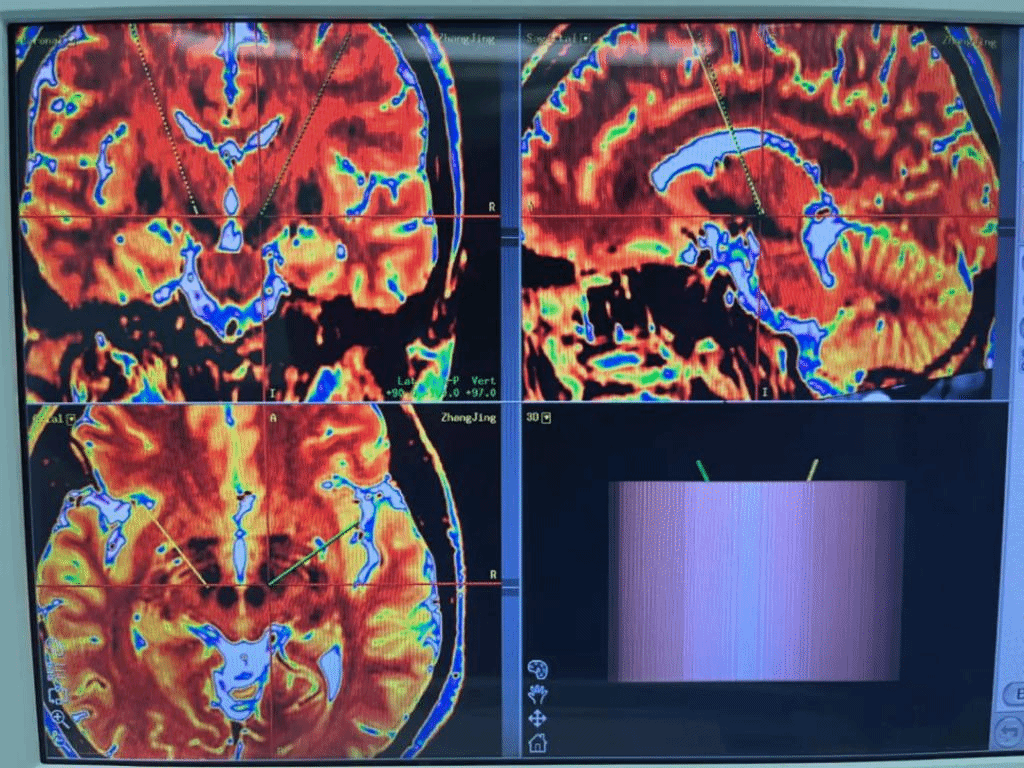

手术前日,神经外四科团队为患者进行了术前预计划、靶点预定位。3.0T磁共振兼容可充电脑起搏器的植入需要比以往更加精准的定位和操作,结合张女士临床表现与病史,团队决定植入以丘脑底核(STN)为植入靶点。手术当日,准确计算出靶点坐标后,团队顺利植入电极,张女士目前状态良好,手抖等症状已获得好转。